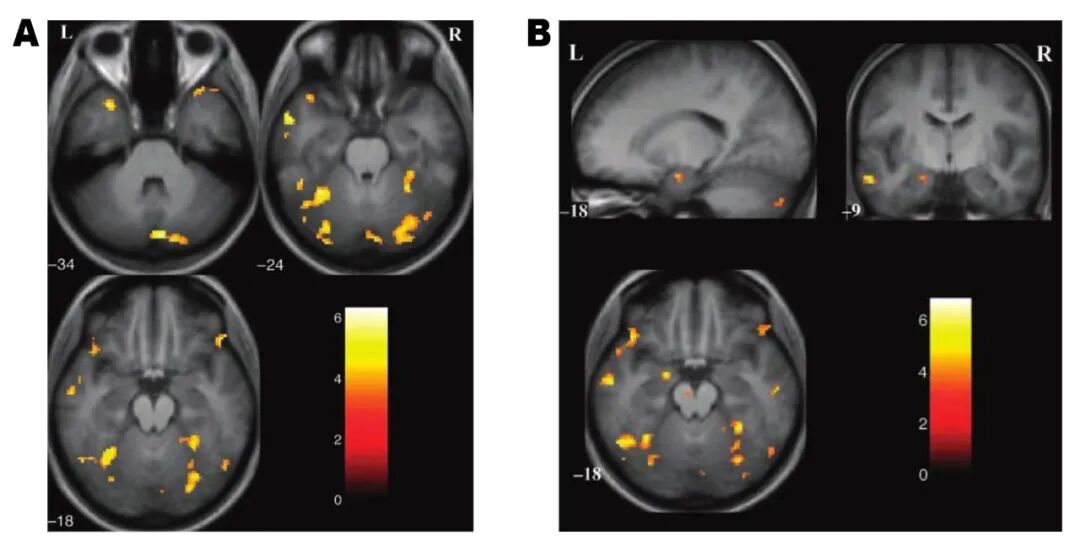

图2.功能性磁共振影像显示与幽默相关的活跃脑区,图A为看卡通幽默漫画时激活的脑区,图B为欣赏理解幽默过程中活跃的脑区。

图2参考文献[3]